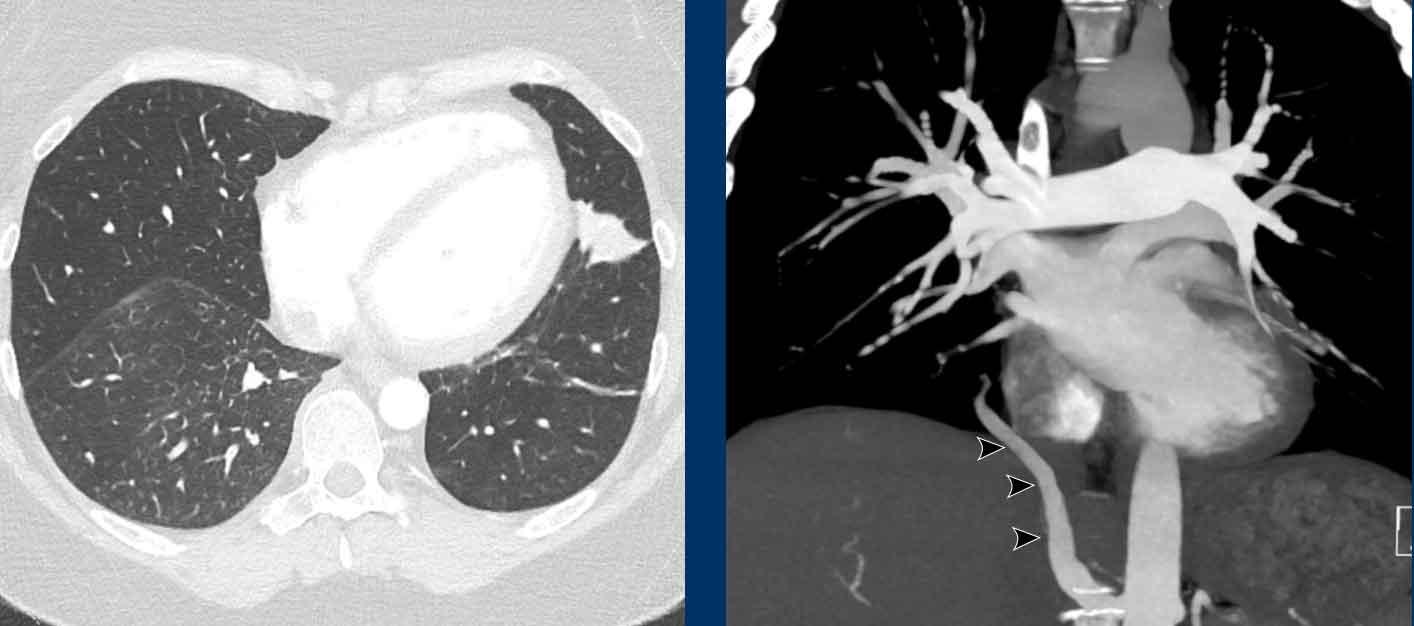

Hình ảnh

Bệnh nhân này được lên kế hoạch cắt thùy trên phải do ung thư phổi và bất thường mạch máu này ban đầu đã bị bỏ sót trên hình ảnh CT.

Những hệ quả trong phẫu thuật của bất thường như vậy nhấn mạnh tầm quan trọng của việc không bỏ sót các biến thể này.

PAPVR bên trái phát hiện tình cờ với dẫn lưu trên tim của máu từ thùy trên trái vào tĩnh mạch tay đầu trái (các mũi tên).